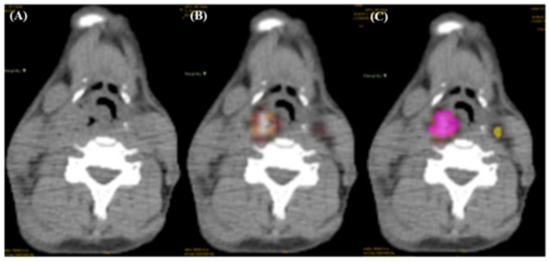

2.3. Tumor Region Delineation